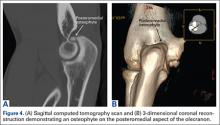

Imaging is essential to the accurate diagnosis of VEO and related conditions. Anterior posterior (AP), lateral, and oblique radiographs of elbow (Figures 3A-3C) may show posteromedial olecranon osteophytes and/or loose bodies. Calcification of ligaments or other soft tissues may also be seen. An AP radiograph with 140° of external rotation may best visualize osteophytes on posteromedial olecranon.18 A computed tomography scan with 2-dimensional sagittal and coronal reconstruction and 3-dimensional surface rendering (Figures 4A, 4B) may best demonstrate morphological abnormalities, loose bodies, and osteophytes. Magnetic resonance imaging (MRI) is essential for assessment of soft tissues and chondral injuries. MRI may detect UCL compromise, synovial plicae, bone edema, olecranon, or stress fractures.